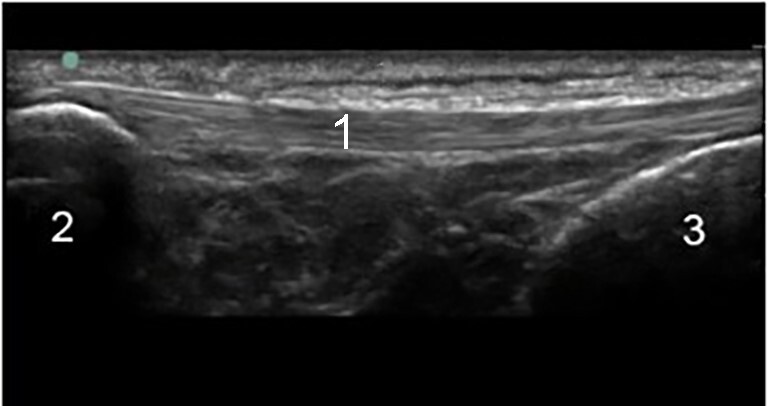

Knee Infrapatellar Tendon Longitudinal Image

Infrapatellar Tendon

Patella

Tibia